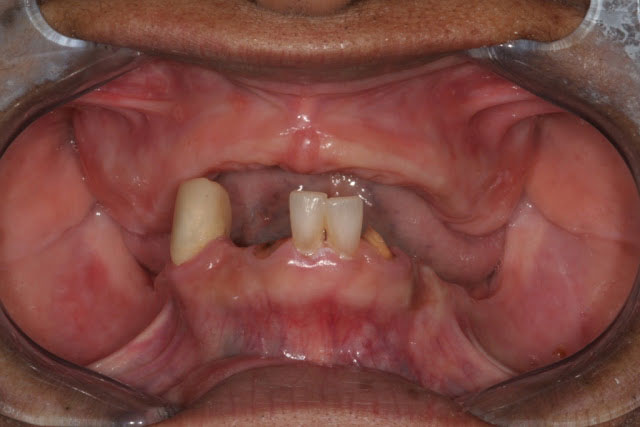

The clinical changes observed when an edentulous maxillary arch is opposed by a mandible with retained anterior teeth that may or may not be extruded and missing posterior teeth. Over time, there is a loss of bone in the premaxilla and in the edentulous posterior mandible, overgrowth of the maxillary tuberosities, and hyperplasia of the hard palate mucosa. Also referred to as anterior hyperfunction syndrome, or Kelly syndrome.